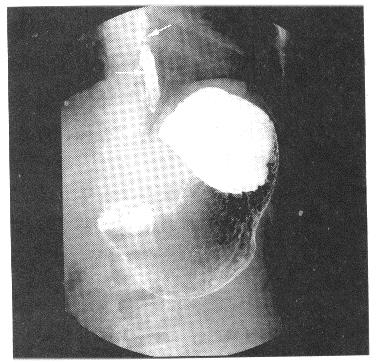

患者,男,42岁。吞咽阻挡感6个月,食管钡餐见图。最可能的诊断是()。

A、食管炎

B、食管癌

C、食管Crohn病

D、食管静脉曲张

E、食管贲门失弛缓症

正确答案:

D